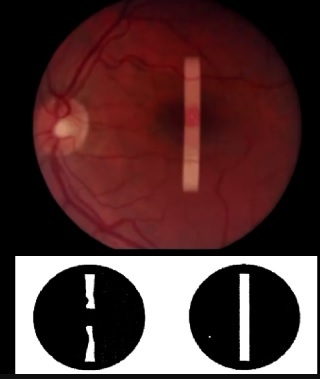

O que é o Sinal de Watzke-Allen?

Visualização de uma Faixa de Luz com uma interrupção no meio, pelo paciente com BM, quando iluminamos a região macular com uma iluminação em fenda.